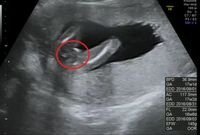

17週の赤ちゃんエコー画像です 男の子か女の子かわかりますか 先生は女の子 Yahoo 知恵袋

赤ちゃんの性別が分かってくるのは、大体17~25週 (5~7ヶ月)ごろと言われています。 早い方だと14週(4か月)くらいに分かるという方も! やはり男の子だと、おちんちんの形で 画像あり妊娠6ヶ月(妊娠週21週22週23週)の胎児の大きさやお 妊娠・出産 1797 助産師さん伝授!産後のカチカチの固いおっぱいの治しかた!乳腺炎になる 妊娠・

男の子の性別判定はいつから可能? 男の子の性別判定はいつから可能なのでしょうか? 男の子の性別判定は比較的早く、早くて15週・16週ごろからシンボルが見えてくる ようです!